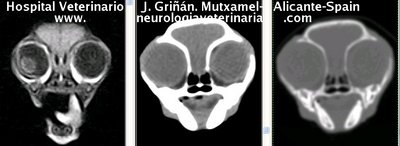

Se muestran cortes transversales de Resonancia Magnética (imagen a la izqda del lector), TC contrastado para tejidos blandos (imagen del centro) y TC contrastado para tejidos duros (imagen de la derecha del lector).

Nótese como la Resonancia supera al TC en el contraste de tejidos blandos (encéfalo y médula espinal) y en el de líquidos (ojo y líquido cefalorraquídeo), mientras que el TC supera a la resonancia en el contraste de tejidos duros (hueso) y aire (senos, cavidad nasal y bullas)

Cortes a nivel del diencéfalo (hipófisis) y lóbulos piriformes. Nótense sendos ventrículos laterales y tercer ventrículo